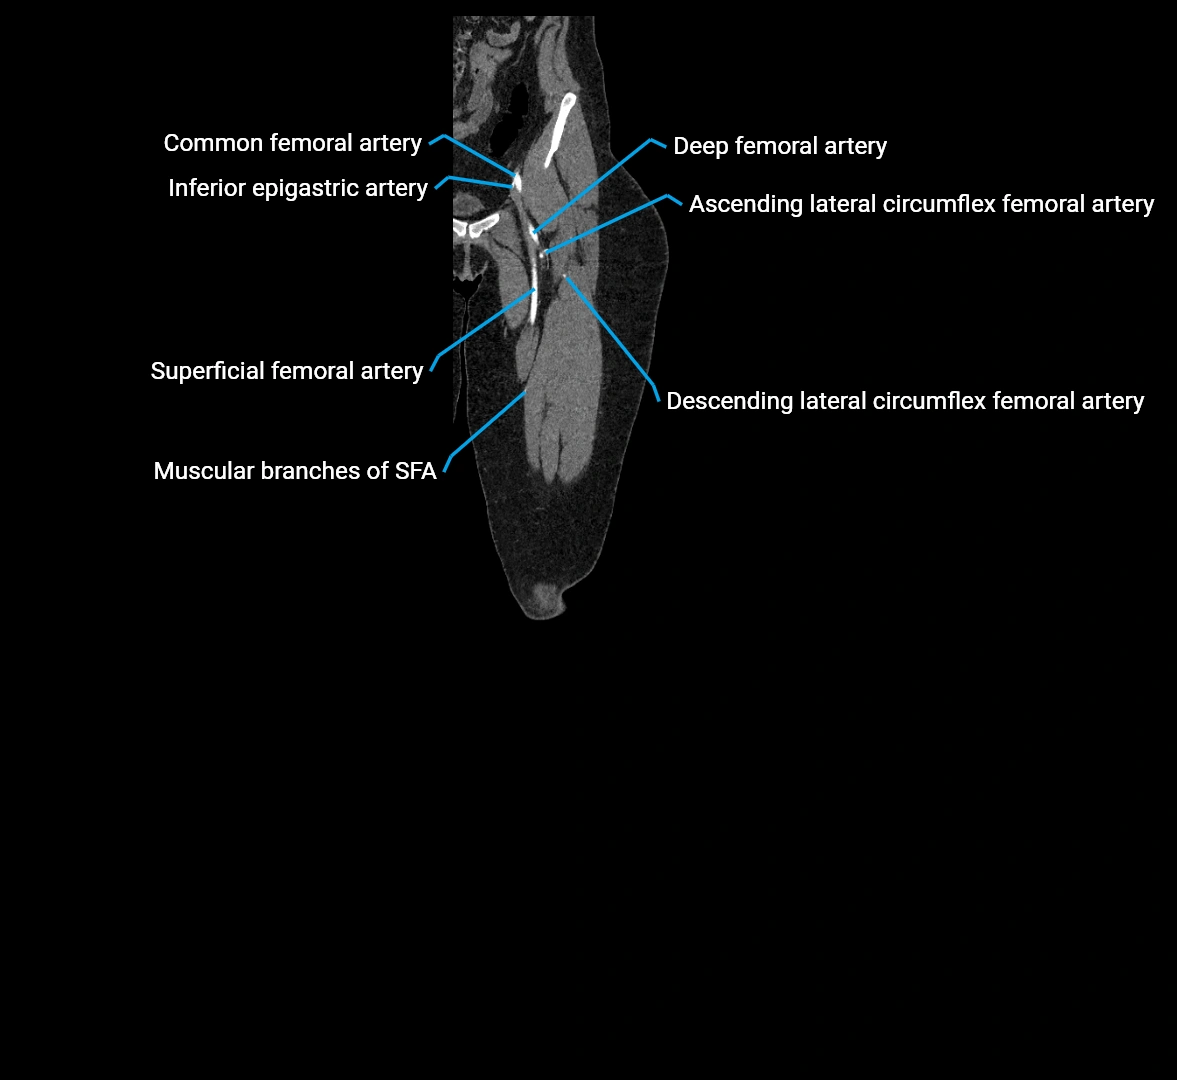

Contrast-enhanced CT (CTA):

• Gold standard for abdominal aortic imaging

• Provides excellent detail of lumen, wall, aneurysm, thrombus, and branch vessels

• Multiplanar and 3D reconstructions help in aneurysm measurement, stent graft planning, and dissection evaluation

• Detects acute rupture, traumatic injury, or occlusion with high sensitivity